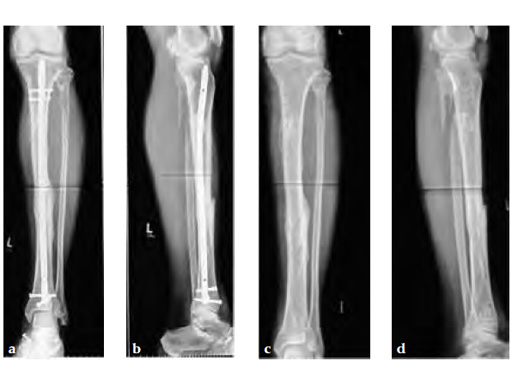

A 58-year-old male sustained a closed multifragmentary 42-C1 fracture in the distal tibia with compartment syndrome.

Case provided by Dankward Hntzsch, Tbingen, Germany

Primary treatment consisted of an external fixator and release of compartments.

Mobilization of the limb started with an applied external fixator.

Secondary treatment: insertion of an unreamed intramedullary nail with three ASLS screws inserted distally providing angular stability.

Partial weight bearing started on postoperative day 2 (with 2030kg). The weight was gradually increased over the following weeks. At 6 weeks, the patient was able to fully bear weight even though a high fibula fracture was present and no callus had yet formed. This suggests that angular stable interlocking of the nail markedly enhances stability. The patient was able to bear weight faster than planned and full weight bearing was possible with little pain.